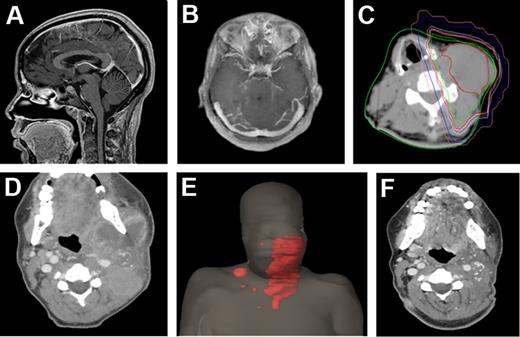

All 20 disease sites treated were symptomatic before irradiation. Patients received radiotherapy to lymph nodes (n = 8; Figure 1), cutaneous lesions (n = 10), whole brain for leptomeningeal disease (n = 1), and a unilateral orbit (n = 1).

Extent of disease among the ATL patient cohort. CT slices in the sagittal (A) and axial (B) planes of a patient with leptomeningeal disease. (C) CT slice in the axial plane of a patient with extensive cervical neck lymphadenopathy. The patient was treated with a right anterior oblique and left posterior oblique photon beam arrangement to gross adenopathy, contoured in red, with radiation isodose lines also depicted (green indicates 102% of the prescribed dose; red, 100%; yellow, 99%; lavender, 98%; cyan, 95%; dark blue, 50%; and pink, 20%). (D) Disease extent in another patient with bilateral, left greater than right, cervical and supraclavicular lymphadenopathy depicted in the axial plan and (E) as a 3-dimensional body reconstruction image with gross tumor contoured in red. (F) Treatment response of the same patient depicted in panels D and E, shown in the axial plane at 7 weeks after photon radiation therapy to the left neck only. A strong partial response to radiation therapy was obtained in this patient.